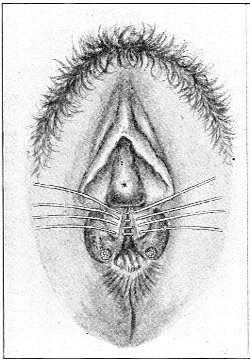

Fig. 16.—Appearance of the external genitals in a woman with gonorrhea: G. m., gonorrheal macula situated at the base of a vaginal caruncle.

Suppuration of the duct may be demonstrated by pressing over the course of the duct, when a drop of pus will escape from the opening. In such cases the orifice of the duct is usually surrounded by a red areola, resembling a flea-bite, which has been called the gonorrheal macula (Fig. 16). This macula persists long after all other traces of inflammation about the vulva and vagina have disappeared, and after all frank suppuration in the duct has subsided. Its presence indicates at least the probability of previous gonorrheal infection.